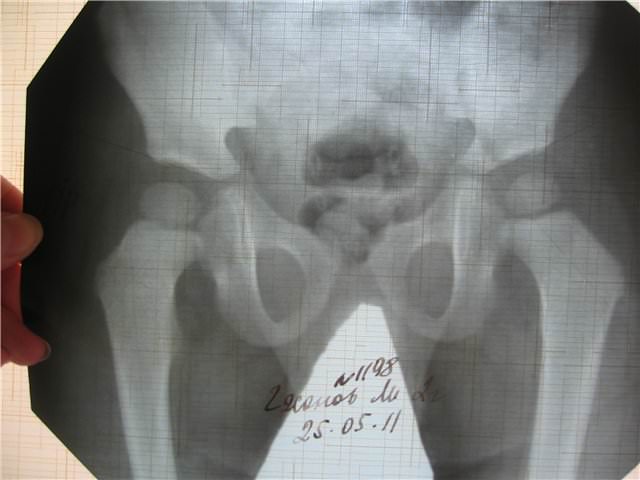

Строение тазобедренного сустава

Технология проведения

Рентген тазобедренного сустава даёт возможность обследовать прилегающие области бедренной кости и некоторых других костей, например, подвздошной. На расположенные рядом участки тела надеваются специальные защитные пластины из свинца, для того чтобы сберечь от ненужного облучения. Одежду, украшения пациент снимает.

Тазобедренный сустав

Рентген таза делают на специальном столе. Тазобедренный сустав снимают обычно в двух проекциях, при необходимости делают больше снимков. Первая проекция – вид спереди, проекция передней и задней тазовых частей. Вторая – вид сбоку, ноги при этом вытягивают, это проекция боковой части. Обычно делают снимки обоих суставов, то есть левого и правого. Это нужно для установления правильного диагноза, даже если жалобы только на боль с одной стороны.

Для получения качественных снимков нужно лежать, не двигаясь. Важно исполнять все рекомендации рентгенологов. Обследование длится недолго, примерно 10 минут.

Расшифровка рентгеновских снимков

Рентгенография может иметь определенные погрешности. Это происходит из-за того, что рентгеновские лучи, которые посылает электронно-лучевая трубка, расходятся потоком. Если предмет исследования находится не посередине, а на краю поля снимка, изображение способно немного удлиняться. В этом случае видоизменяются также размеры исследуемых суставов.

Точность постановки диагноза во многом зависит от того, насколько квалифицированным является врач-лаборант. Каждое заболевание обладает своими характерными чертами, которые выявляются на снимках:

- переломы – видны костные отломки;

- вывихи – можно увидеть смещение суставных поверхностей;

- остеоартроз – сужение суставной щели, остеофиты;

- асептический некроз – костная регенерация, очаги остеосклероза;

- остеопороз – хорошо видна истонченная структура, сниженная плотность кости;

- дисплазия – обнаруживается неполное или неправильное развитие головки бедра вместе с суставной впадиной;

- опухоли – очаги затемнения, объемные образования.